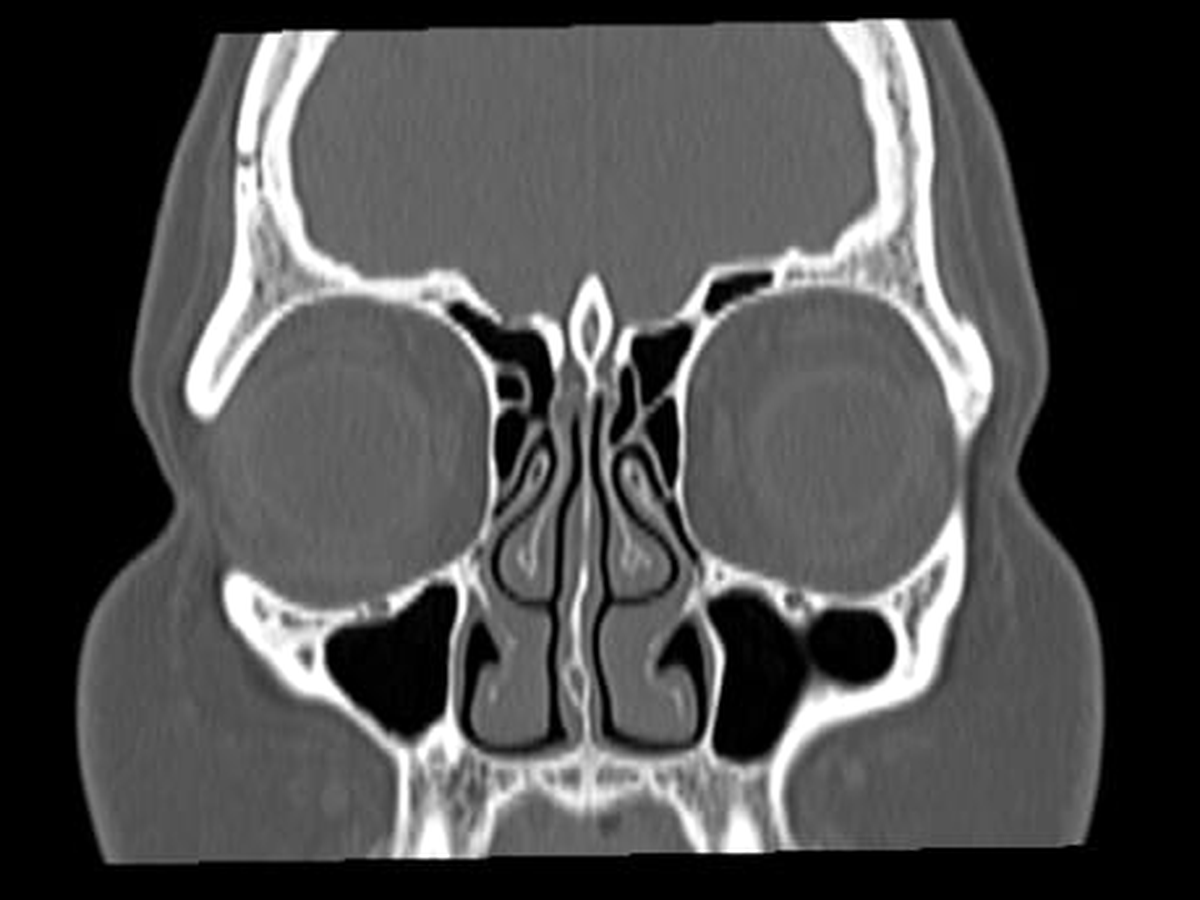

En los últimos meses, Jas comenzó a presentar un síntoma alarmante: fuga de líquido cefalorraquídeo a través de las fosas nasales, causada por una fisura en el tejido cerebral y presión craneal elevada. Tras semanas de estudios, consultas con especialistas y un proceso de diagnóstico que no ha sido fácil, Jas fue sometida a una cirugía para corregir la fuga.

Durante este proceso, los médicos también le diagnosticaron Síndrome de la Silla Turca Vacía, una condición que requiere atención neuroendocrinológica continua.